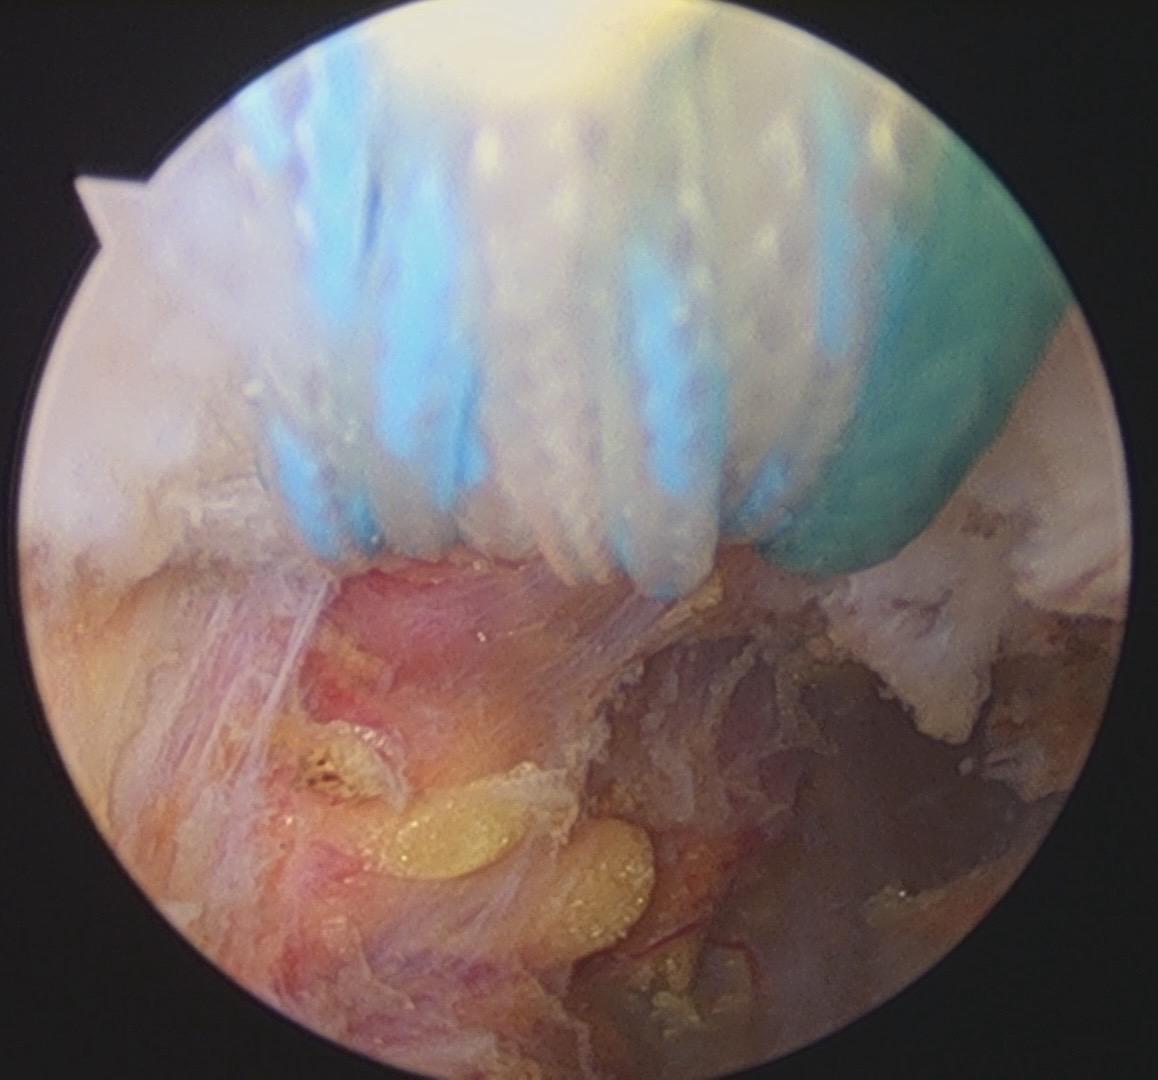

肩锁关节脱位。手术台上的每一次突破,都离不开前辈的倾囊相授。感谢赵立连主任的悉心指导,从理论到细节。